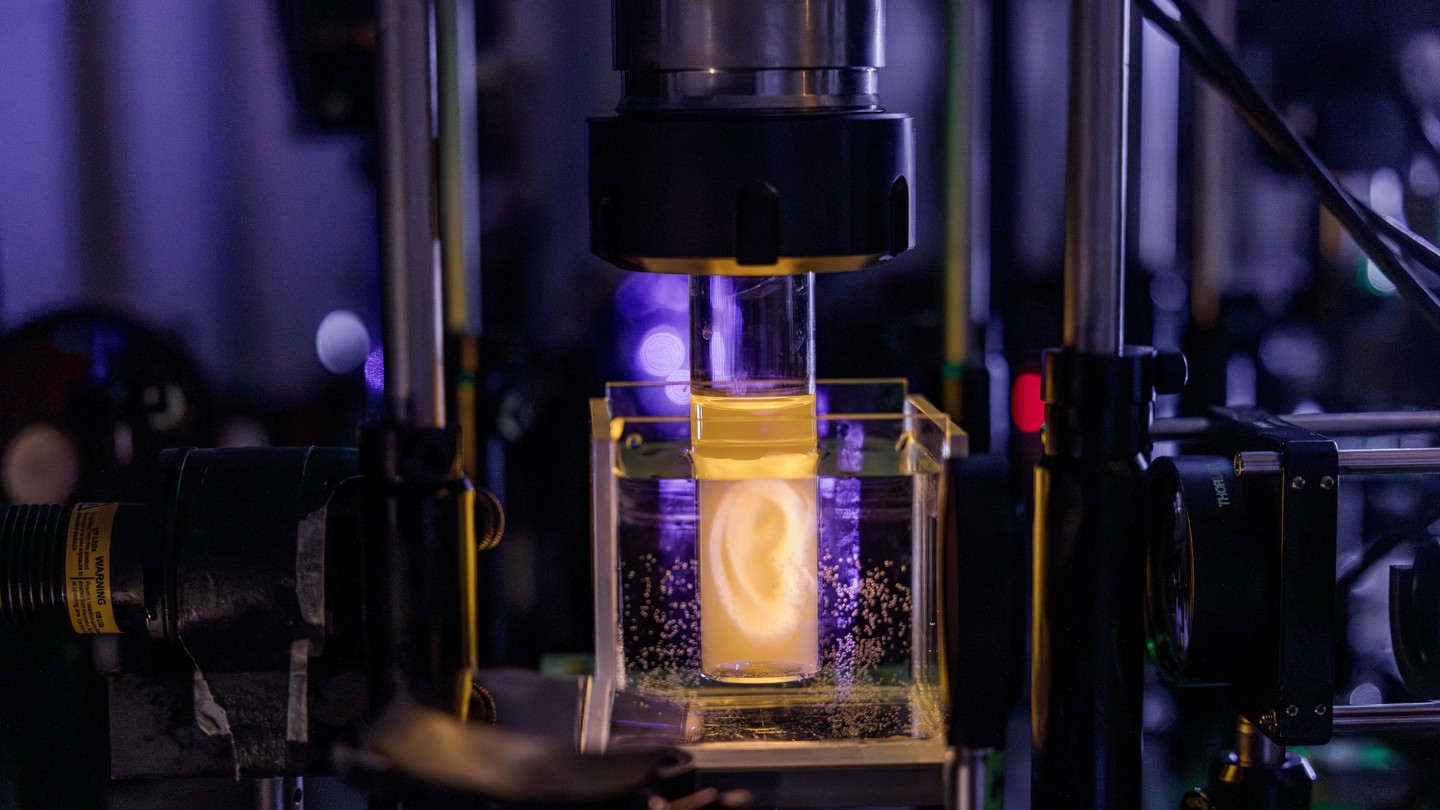

A travers ses différents campus, l’EPFL bénéficie d’une communauté de recherche plurielle, engagée et stimulante, active sur un large éventail de disciplines axées sur l’innovation. Pour encourager la recherche transdisciplinaire, nous lançons des initiatives stratégiques telles que le Swiss National AI Initiative, le Swiss Plasma Centre ou le Swiss Data Science Center. Nous abordons des thématiques critiques de recherche telles que la science des données, la santé personnalisée, le génie biomédical, l’énergie, la robotique et la fabrication de pointe, afin de relever des défis sociétaux cruciaux tout en garantissant que la Suisse reste à la pointe de la technologie moderne. Notre communauté de recherche et la science qu’elle produit sont ouvertes sur le monde : nous partageons les connaissances que nous produisons, nous faisons participer le grand public et nous avons de nombreuses collaborations et partenariats avec d’autres institutions, laboratoires de recherche ainsi qu’avec l’industrie.

Découvrez l’infrastructure de pointe de recherche de l’EPFL offrant des services.